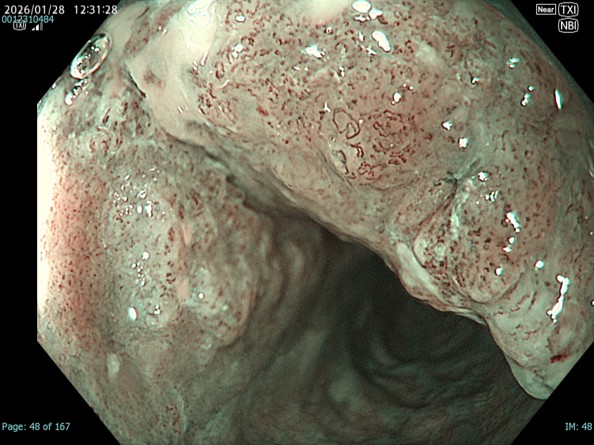

• NBI+TXI観察(近景)

切替前 NBI強調設定:A8

NBI+TXIレベル:高

図8 図7 図9

NBI観察と比較するとDLが明瞭であり、この後行うESDにおいてもマーキングに有用であった。